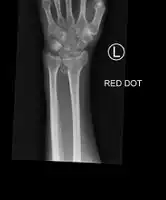

Colles fracture

Diagnosis can be made upon interpretation of anteroposterior and lateral views alone.[6]